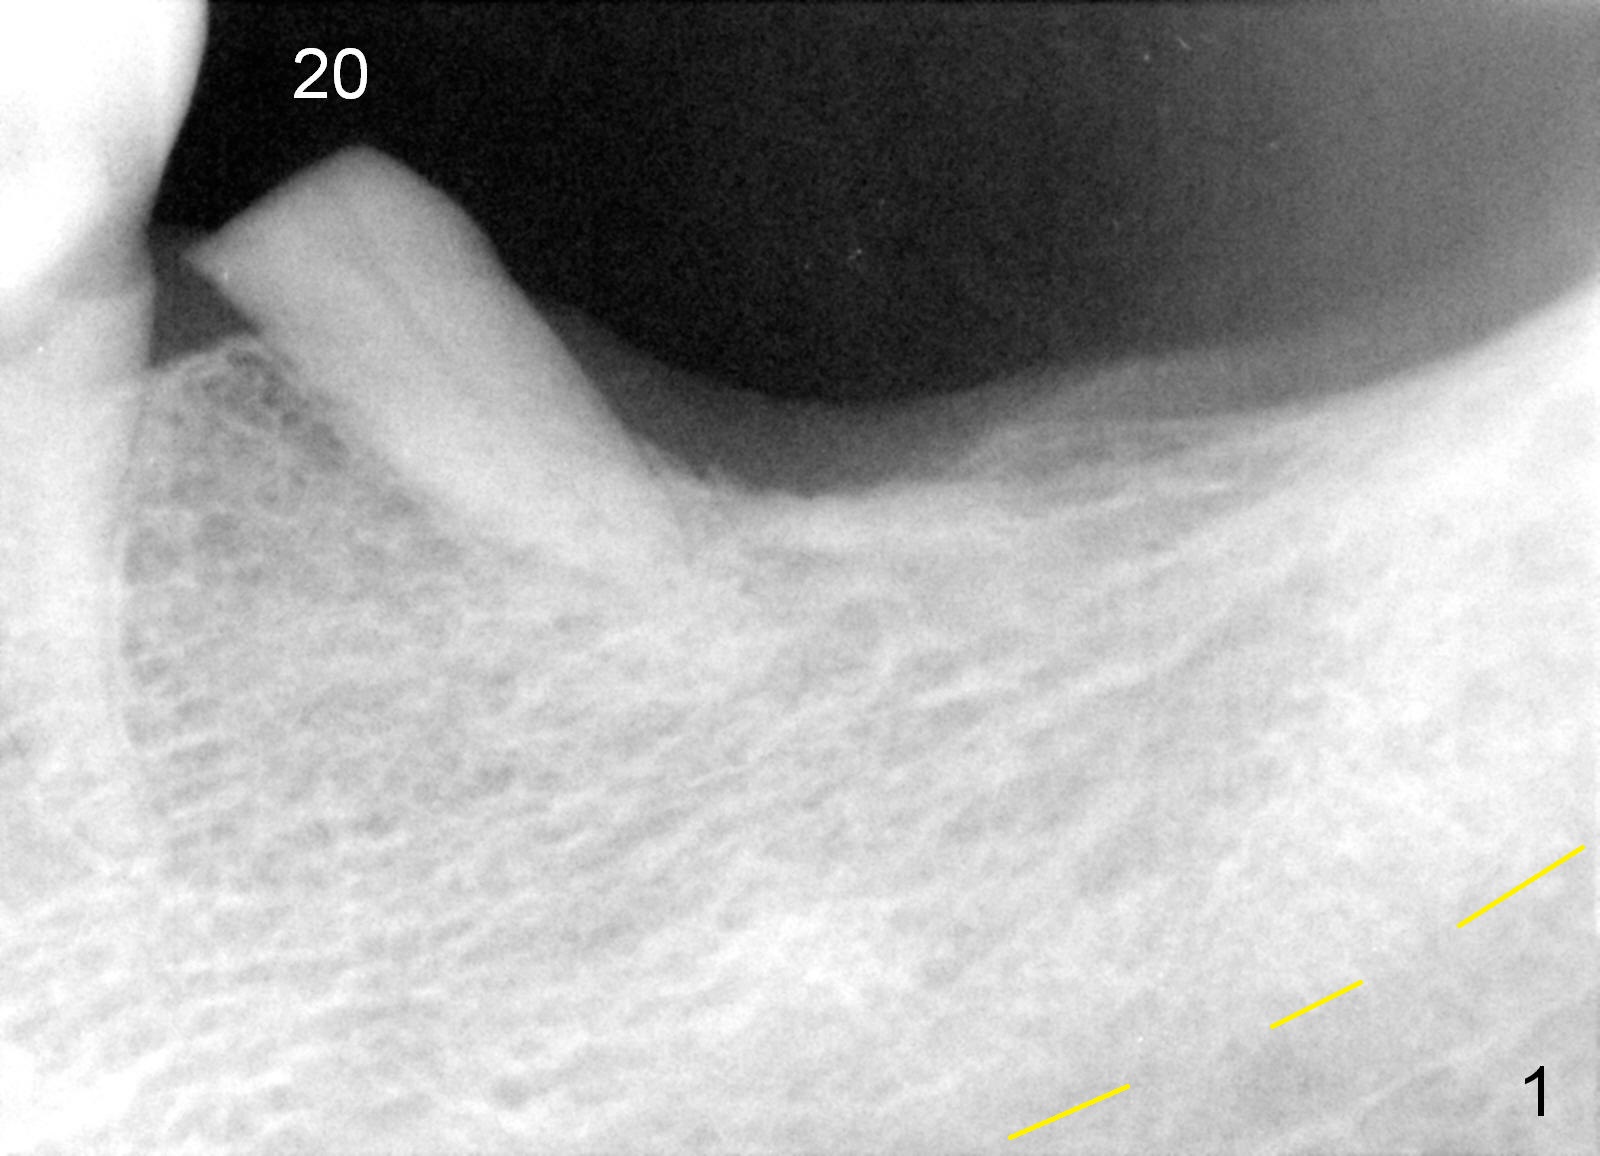

A 78-year-old lady is scared of dentistry, but she has no problem having a 2nd immediate implant (#20 in Fig.1) once the 1st one turns out to be without pain. The challenge associated with #20 is its long axis. After extraction, the osteotomy is initiated in the mesial socket wall at the junction of the upper and middle 1/3 obliquely (Fig.2, slightly lingually). Once the entry is obtained, the axis of the pilot drill is changed to be parallel to the neighboring tooth (Fig.3); an implant spacer of 2.5 mm is used to check (against the 2 mm pilot drill) so that the center of the osteotomy is 3.5 mm from the neighboring tooth (Fig.4). The implant will be 4.5x14 mm. The depth is not longer than that of the neighboring tooth so that it should be quite safe relative to the Mental Loop and the Inferior Alveolar Canal (yellow dashed line in Fig.1). The apical socket is packed with collagen dressing while the coronal one with bone graft. An immediate provisional will be fabricated to keep the graft in place. The osteotomy should be as lingual as possible to avoid the Mental Loop (Fig.1' red dashed line).